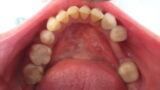

初診で来院されましたが会議の為早急に製作して下さいと言われて、1週間ちょっと仕上げました。